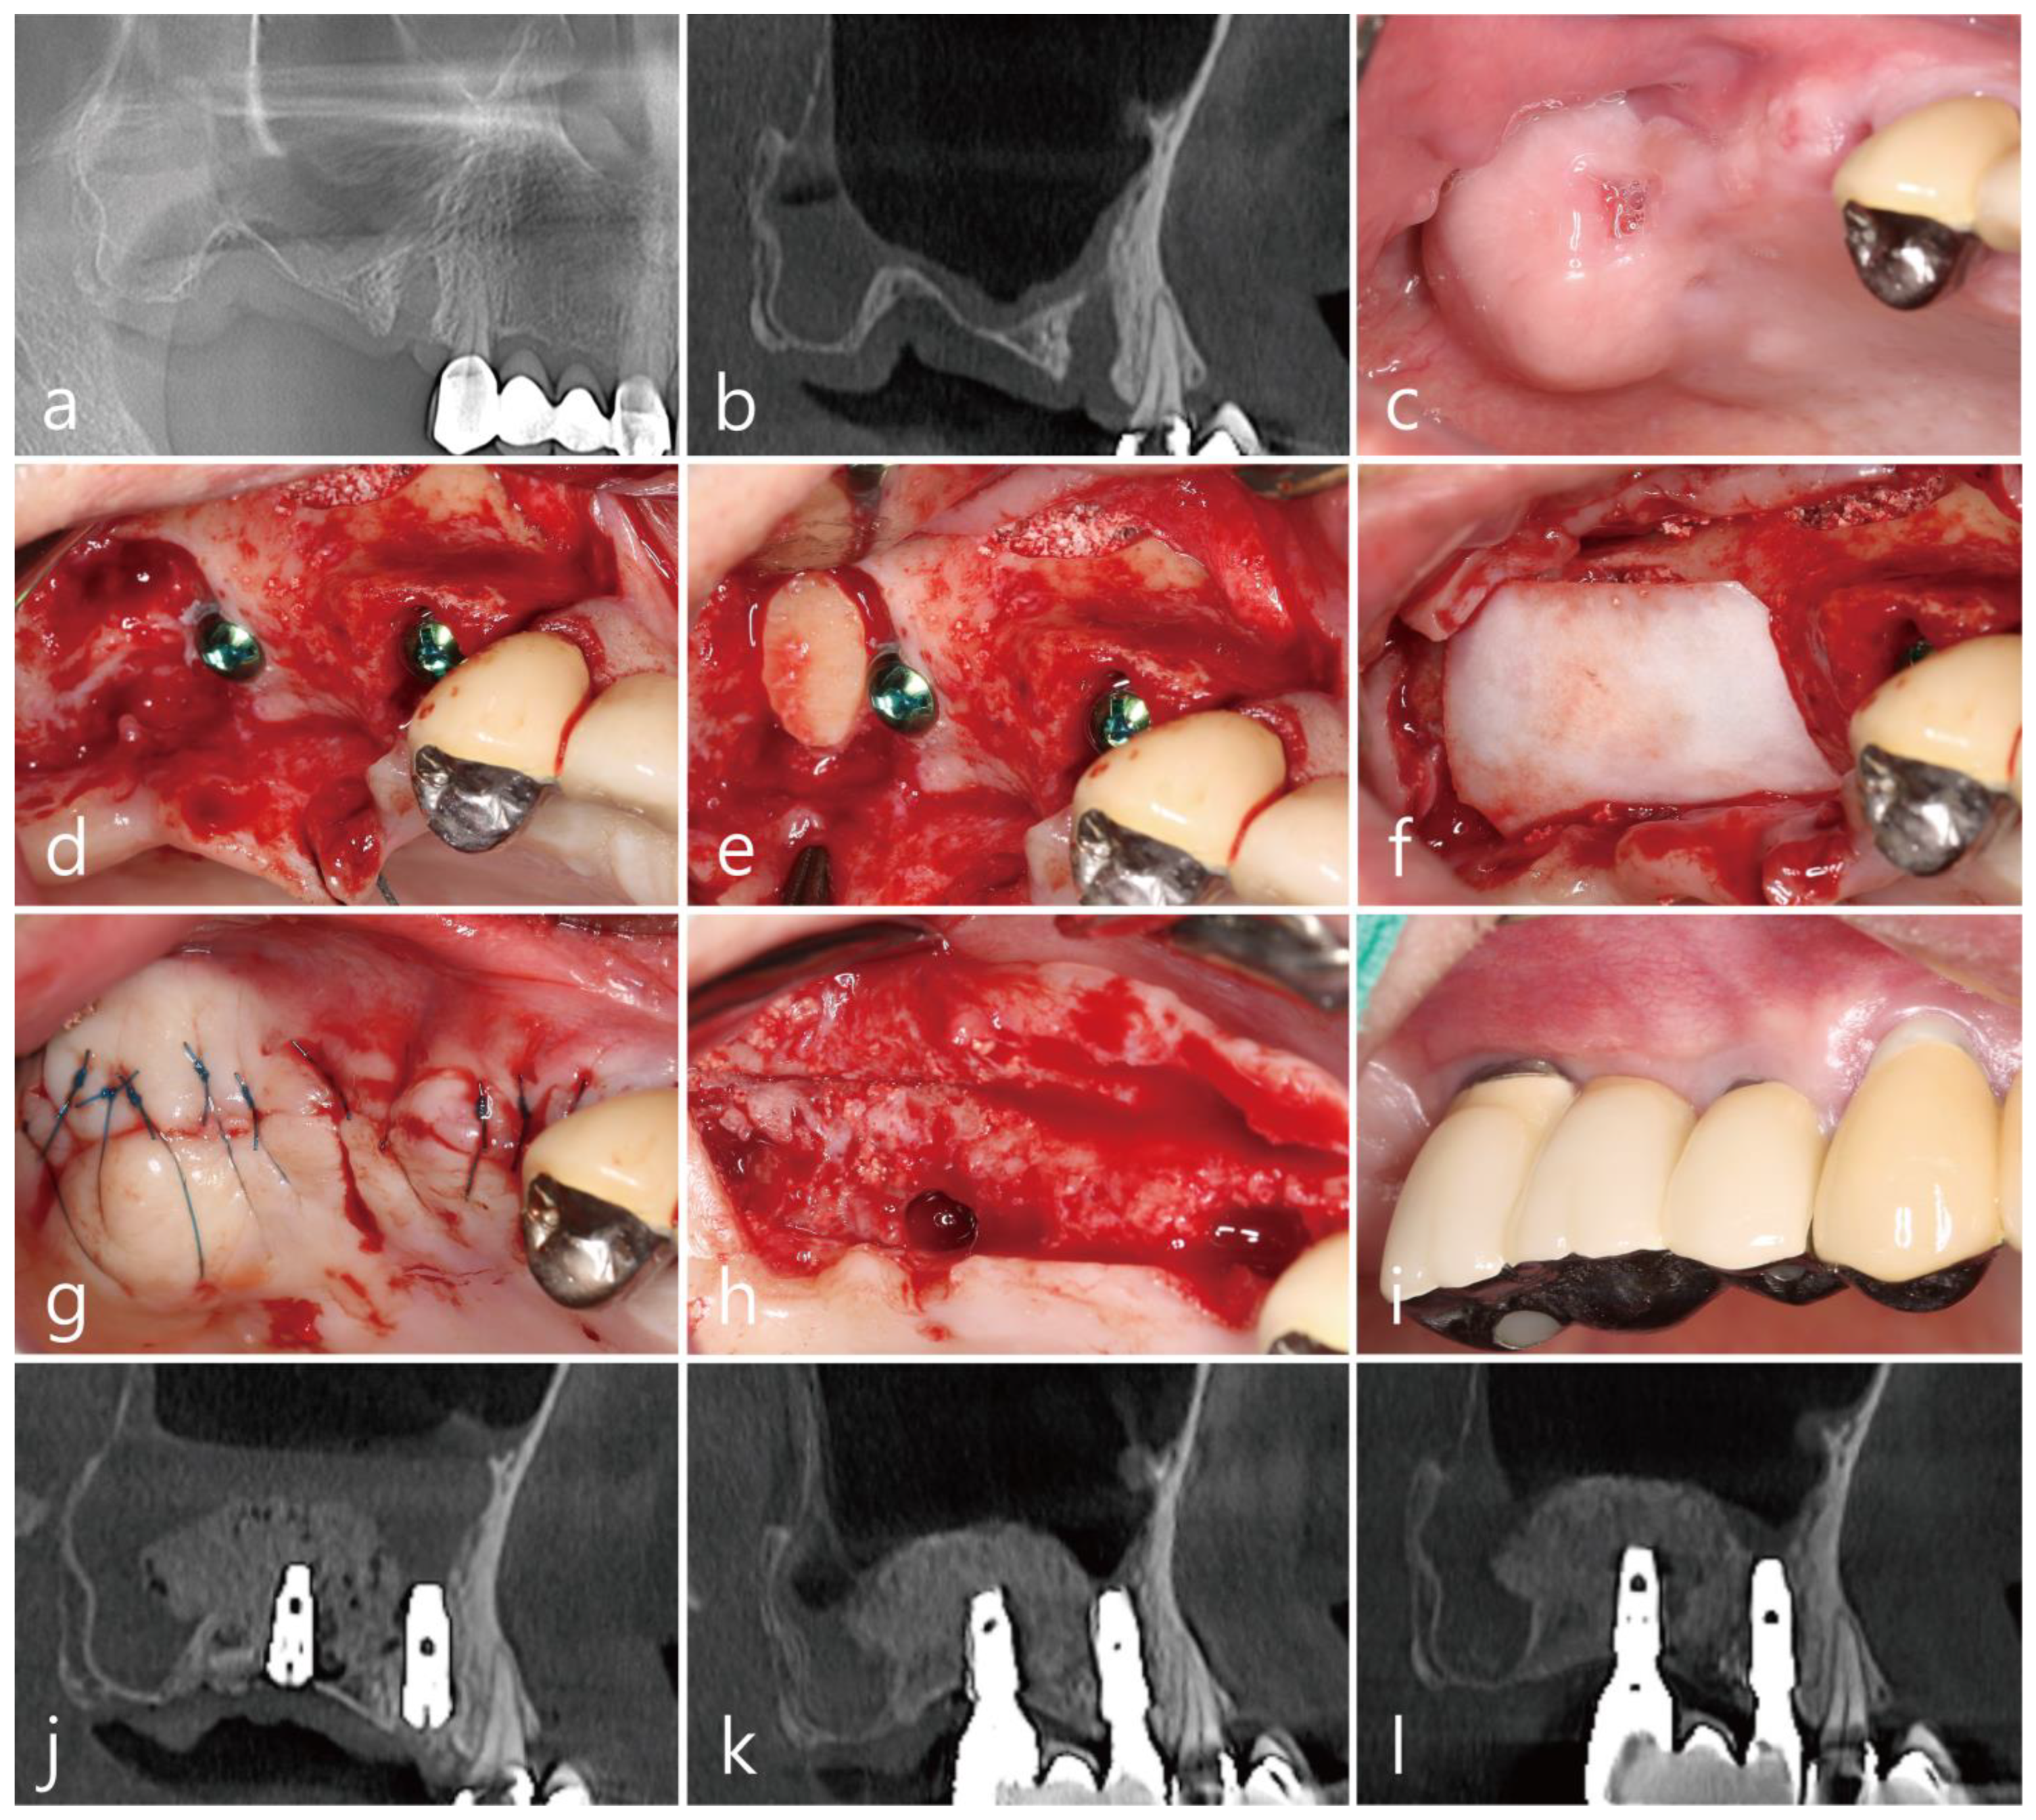

The patient was a 72 years old nonsmoking female, who visited the clinic for implant placement in the right posterior region of the maxilla (Table 1). She had undergone extractions of the maxillary right second premolar and second molar two months prior. The extraction site of the maxillary second molar exhibited severe vertical bone resorption. In addition, the right maxillary sinus was severely pneumatized (Figure 1a). The sagittal image of the preoperative cone-beam computed tomography (CBCT; RainbowTM CT, Dentium, Suwon, Republic of Korea; exposure time 10 s) scan revealed an intraosseous defect in the extraction site of the maxillary right second molar (Figure 1b). No posterior superior alveolar artery (PSAA) in the lateral sinus wall was observed in the CBCT scans (Table 1). A vertical deficiency of the soft tissue was also observed (Figure 1c). Lateral MSA and simultaneous implant placement were planned. The flaps were reflected under local anesthesia with 2% lidocaine (containing 1:100,000 epinephrine). After the removal of the granulation tissue in the extraction sites, MSA was performed using the lateral window technique with an Osteon II (Genoss Co., Ltd., Suwon, Republic of Korea), and the lateral sinus bony window was obtained. Two SLA-textured implants (Ø4.3 × 12 mm and Ø4.8 × 10 mm; Implantium, Dentium Co., Ltd., Suwon, Republic of Korea) were placed (Table 1, Figure 1d). The obtained lateral sinus bony window was passively placed without fixation to an intraosseous defect on the distal aspect of the implant placed in the right maxillary secondary molar site (Figure 1e). The surgical site was subsequently covered with a resorbable collagen membrane (Genoss Co., Ltd., Suwon, Republic of Korea) (Figure 1f), and the flaps were closed with 5-0 nylon sutures (Figure 1g). Antibiotics (ciprofloxacin 500 mg; Ildong Pharmaceutical Co., Ltd., Seoul, Republic of Korea) and a nonsteroidal anti-inflammatory drug (Etodol; 200 mg; Yuhan Co., Ltd., Seoul, Republic of Korea) were prescribed for 10 days. The sutures were removed after two weeks. Transient post-operative swelling and pain were reported, but healing was uneventful. The uncovering procedure was performed six months after the surgery (Figure 1h). A prosthesis was delivered two months after the uncovering procedure. Two years after prosthesis delivery, no abnormal findings were observed around the implant (Figure 1i). The sagittal view of the CBCT scan performed immediately after surgery shows a well-placed lateral window bone in the distal defect of the implant placed in the maxillary right second molar site (Figure 1j). In the sagittal image of the CBCT scan performed immediately after the prosthesis delivery, the lateral sinus window bone was well incorporated with the surrounding native bone (Figure 1k). The sagittal CBCT scans two years after the prosthesis delivery revealed an improved bony density (Figure 1l).

Figure 1. Case 1: (a) preoperative panoramic radiograph; (b) sagittal image of the preoperative CBCT scan showing a severely resorbed bone defect; (c) preoperative clinical view two months after tooth extraction; (d) after the flap reflection, a lateral window was prepared, and the buccal bony window was obtained during the maxillary sinus augmentation; (e) the obtained lateral bony window was passively placed on the distal intraosseous defect of the #17 implant without fixation; (f) the surgical site was covered with a resorbable collagen membrane; (g) the flaps were closed with minimal tension; (h) the uncovering procedure was performed six months after the operation, and the lateral window bone was well incorporated with the adjacent native bone; (i) clinical view at two years after prosthesis delivery; (j) panoramic radiograph immediately after surgery; (k) sagittal image of the CBCT scans after prosthesis delivery; (l) sagittal image of the CBCT two years after prosthesis delivery, where the lateral bony window was well incorporated with the surrounding native bone, and the bone density was increased.